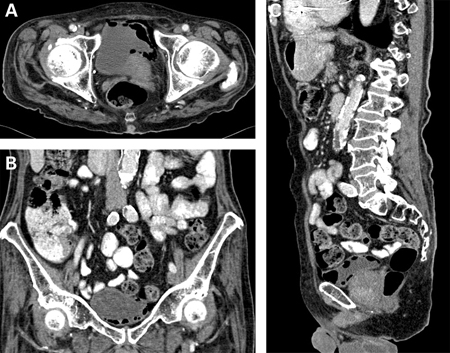

Características como febre, dor ou sensibilidade no flanco, instrumentação recente, imunocomprometimento, episódios recorrentes e anormalidades conhecidas do trato urinário devem ser consideradas sinais de alerta. As causas infecciosas precisam ser identificadas e tratadas imediatamente.[Figure caption and citation for the preceding image starts]: Cistite enfisematosa: (A) corte horizontal de tomografia computadorizada (TC) mostrando enfisema aumentado; (B) corte coronal de TC mostrando enfisema aumentado; (C) corte sagital de TC mostrando enfisema aumentadoMiddela S, Green E, Montague R. Emphysematous cystitis: radiological diagnosis of complicated urinary tract infection. BMJ Case Rep. 2009; doi:10.1136/bcr.05.2009.1832. Usado com permissão [Citation ends].